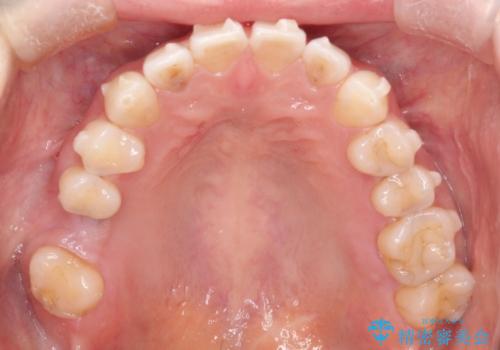

- 過去に矯正を行ったあと、前歯の後戻りを主訴に来院されました。

マウスピース矯正にて隙間を閉じる計画をたて、治療を行いました。